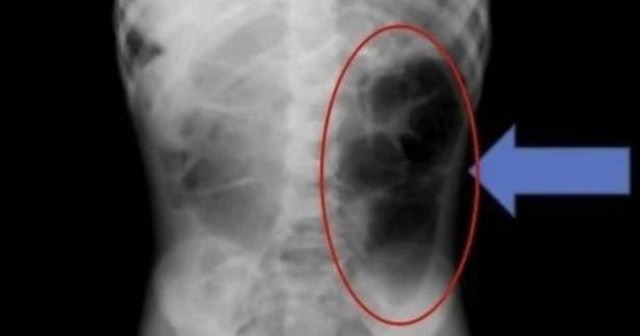

Ngày 20/1, tạp chí y khoa Cureus đã đăng tải trường hợp của một bé gái 6 tuổi, tên A, sống tại Ả Rập Xê Út. Bé A đến bệnh viện vì đột nhiên bị đau bụng và các vấn đề về tiêu hóa. Sau khi thăm khám, các bác sĩ xác nhận có một búi tóc rối bên trong dạ dày của bé.

Nhóm y tế phát hiện ra rằng sợi tóc không chỉ nằm trong dạ dày mà còn lan đến ruột non. Họ cho biết: "Nếu bệnh nhi có các triệu chứng dai dẳng như đau bụng tái phát, nôn mửa hoặc chán ăn kéo dài, cần phải xem xét khả năng có dị vật trong đường tiêu hóa".

Búi tóc được phát hiện trong bụng bé gái.